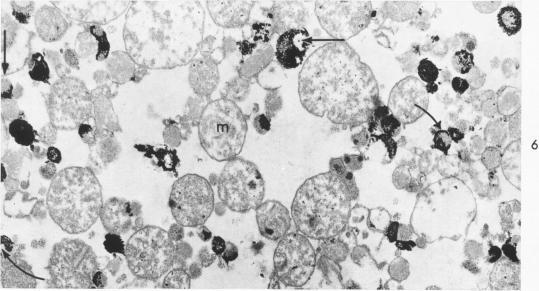

Disruption of Kupffer cells during systemic anaphylaxis in the mouse. I. Properties and distribution of heat- and formaldehyde-stable liver acid p-nitrophenylphosphatase.

Am J Pathol. 1967 Oct;51(4):483-503.

Abstract

摘要